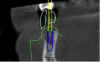

Co-diagnostic software was also used. While this type of software is available to practitioners from multiple manufacturers, in this case the laboratory provided the software. Co-diagnostic software allows for a prosthetically driven implant placement. In other words, the restorative outcome is taken into account prior to planning the placement of the implant. The software enables the team to incorporate the scanned image of the arch and the CBCT data to plan the surgery and fabricate a surgical stent, if so desired.12

This software allows accurate visualization of anatomic structures that are to be avoided during placement. This was especially important in this case because of the close proximity of the inferior alveolar nerve to the proposed implant sites. This planning has been found to lead to optimal results and allows the surgeon to place implants safely and efficiently.13-15

Once the scan and CBCT were loaded into the software, the respective files were merged to create a new image (Figure 2 through Figure 5). The data was then analyzed. The available software has vast libraries, some with up to 3,000 implant components from which to choose, from various manufacturers.12 The appropriate anterior-posterior position was determined, followed by the proper diameter and length of the implant bodies. This was all determined with the restoration in mind. The data was then used to fabricate a guide for the surgeon to use (Figure 6). These decisions were all made collectively by the team.